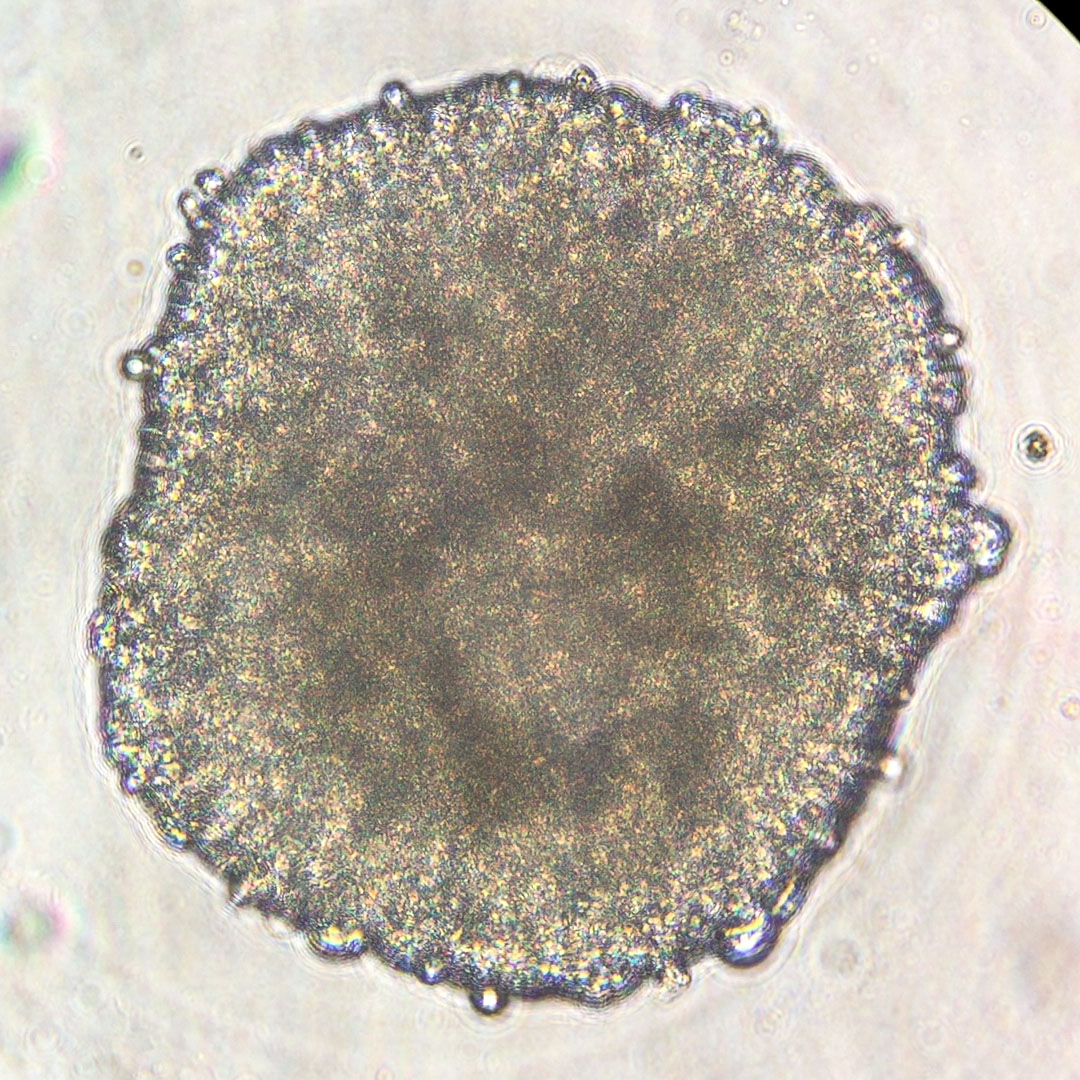

The Tissue Chips in Space program, a collaboration between the National Center for Translational Sciences at the National Institutes of Health and the ISS National Lab, is sending up its final two studies. Both are second flights of heart-related investigations that use tissue chips, small devices that mimic functions of human organs.

Cardinal Heart 2.0 builds on the Cardinal Heart investigation. That study, according to Dilip Thomas, a post-doctoral researcher at the Stanford Cardiovascular Institute, affirmed the hypothesis that microgravity can adversely influence engineered heart muscle tissues. “This second study aims to test whether clinically approved drugs mitigate the signs of abnormal processes seen from the first flight,” he says.

Principal Investigator Joseph Wu, director of the institute, says the follow-up study could provide a deeper understanding of how major heart cell types respond to drugs in the space environment. That understanding could guide drug development strategies on Earth to treat patients with diseases such as heart failure more effectively.

The first Engineered Heart Tissues investigation looked for changes at the cellular and tissue level that could provide early indication of the development of cardiac disease.

Engineered Heart Tissues-2 tests whether new therapies prevent these negative effects from occurring. This research could help predict and prevent cardiovascular risk and lead to countermeasures to protect future space explorers. Because the cardiovascular system’s response to microgravity resembles age-related diseases on Earth, these studies could help patients at risk of developing heart disease on the ground as well.